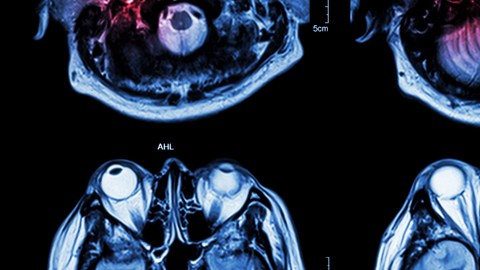

Actuar con rapidez ante un derrame cerebral puede salvar vidas. Crédito: Shutterstock